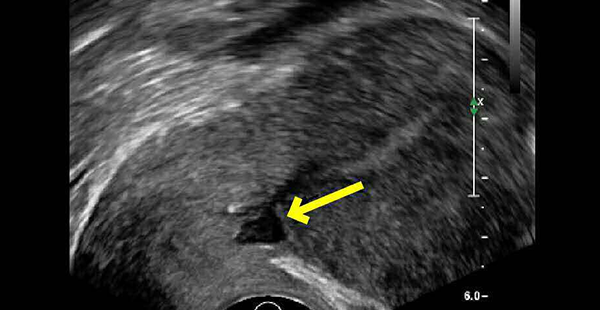

(3)三维经阴道超声(TVUS)、子宫输卵管造影(HSG)、注水宫腔声学造影(SHG)、MRI及宫腔镜检查等辅助检查,有憩室的特征性表现。